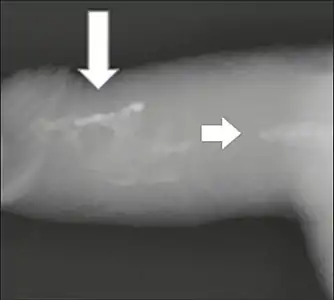

Projectional radiography ("X-ray"), penetrating the soft parts of the penis, showing radiopaque images that correspond to calcifications in the corpora cavernosa (arrows).

On penile ultrasonography, the typical appearance is hyperechoic focal thickening of the tunica albuginea. Due to associated calcifications, the imaging of patients with Peyronie's disease shows acoustic shadowing, as illustrated in figures below. Less common findings, attributed to earlier stages of the disease (still mild fibrosis), are hypoechoic lesions with focal thickening of the paracavernous tissues, echoic focal thickening of the tunica without posterior acoustic shadowing, retractile isoechoic lesions with posterior attenuation of the beam, and focal loss of the continuity of the tunica albuginea. In the Doppler study, increased flow around the plaques can suggest inflammatory activity and the absence of flow can suggest disease stability. Ultrasound is useful for the identification of lesions and to determine their relationship with the neurovascular bundle. Individuals with Peyronie's disease can present with erectile dysfunction, often related to venous leakage, due to insufficient drainage at the site of the plaque. Although plaques are more common on the dorsum of the penis, they can also be seen on the ventral face, lateral face, or septum.[13]